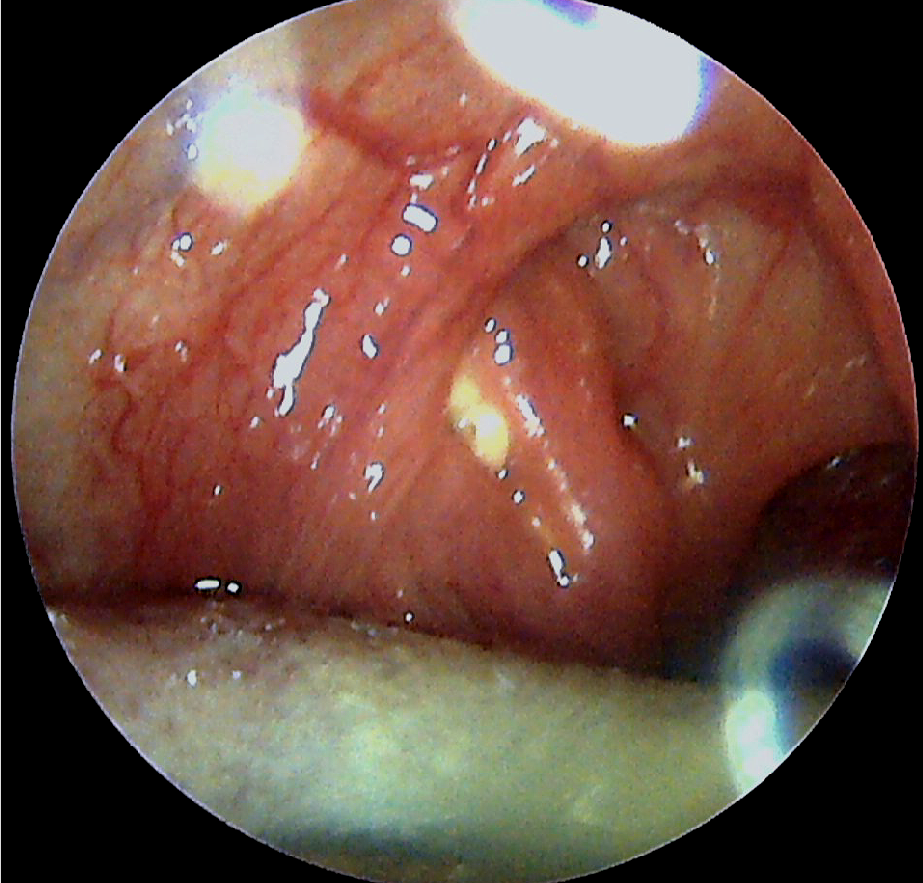

A는 편도선을 덮고 있는 근육인데 이렇게 생긴 근육이 편도선 앞에도 있고 뒤에도 있어요 이들 근육 사이의 공간인 편도선과 (tonsillar fossa)에 편도선이 있습니다. 위의 사진처럼 A근육이 편도선을 가리기 때문에 눈만으로 편도선을 관찰하는 데 한계가 있습니다.

그럼 위 사진의 오른쪽, B위치를 볼까요? 편도선은 눈에 보이는 것 이외에 B의 위치까지 훨씬 아래로 연결되어 있는데, 혀로 덮인 아래쪽 편도는 설압자로 혀를 눌러도 완전히 관찰할 수 없습니다.

A근육과 편도 사이의 공간, 혀에 가려진 아래쪽 편도 B까지 모두 관찰하는데 사용하는 것이 위쪽과 같은 이비인후과 내시경입니다. 이비인후과 의사에게 둘도 없는 무기입니다. 구강 내 가장 깊은 곳의 후두를 관찰할 때 외에도 편도 주변을 꼼꼼히 살펴볼 필요가 있다고 판단되면 이비인후과 내시경을 입 안으로 삽입하여 관찰합니다. 다만, 이비인후과 내시경은 특별한 훈련을 받은 이비인후과 전문의만 실시할 수 있기 때문에 기본 진료비 이외에 몇 천원의 추가 진료비가 발생함을 양해해 주셔야 합니다.(그래도 위 카메라 등에 비하면 매우 저렴합니다.)